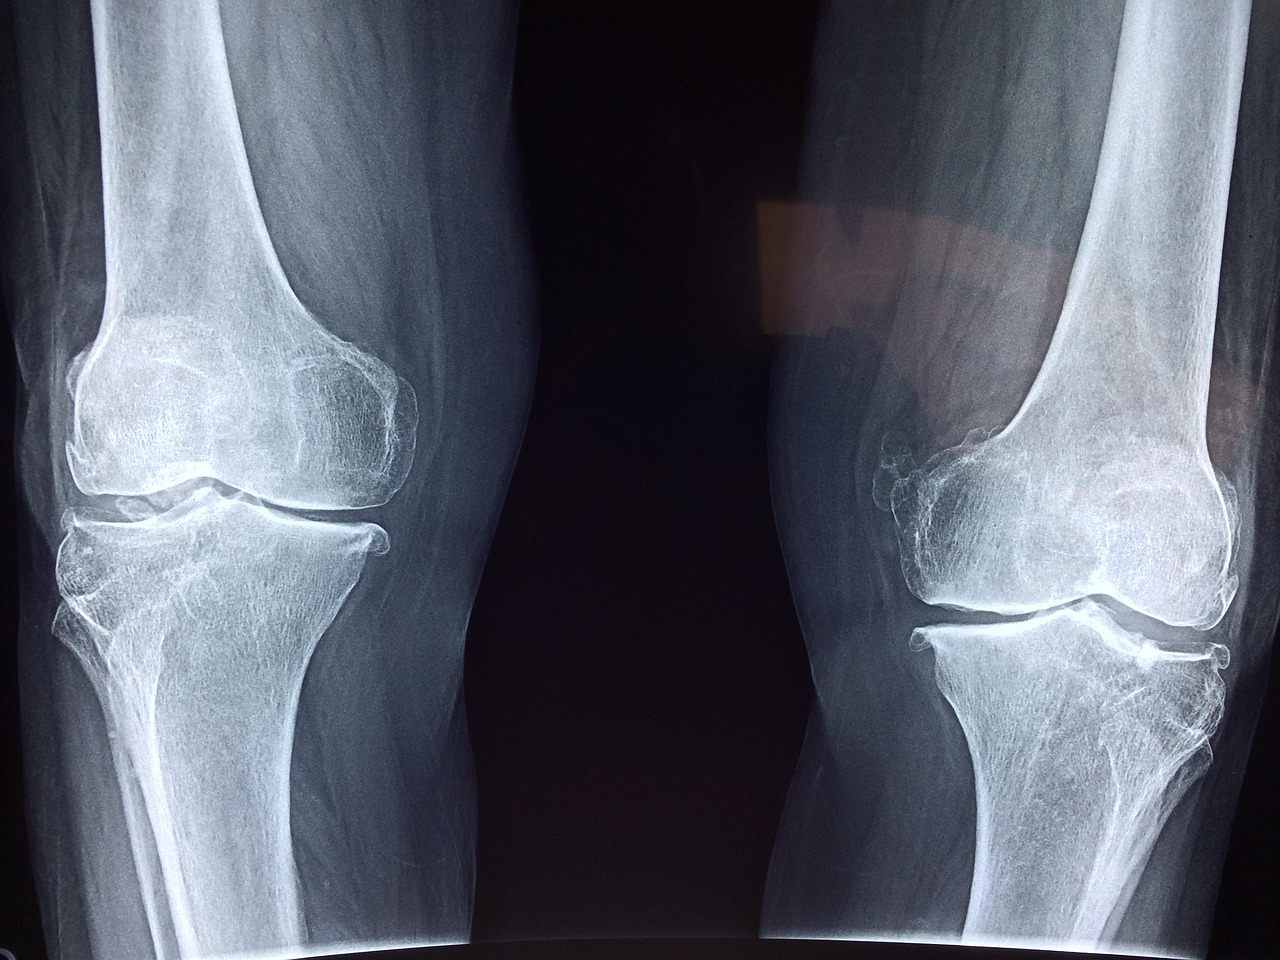

골다공증은 뼈가 약해져 쉽게 골절되는 상태를 말합니다. 그런데 정작 많은 사람들이 골밀도 검사를 받아도 수치의 의미를 잘 모른 채 지나치곤 하죠. 결론부터 말하면, 골다공증 정상수치는 T-score -1.0 이상입니다. -1.0 미만부터는 골감소증, -2.5 미만이면 골다공증으로 진단됩니다.

T-score는 젊고 건강한 사람의 평균 골밀도와 비교한 상대 수치입니다. -1.0 이상은 정상, -1.0 ~ -2.5는 골감소증, -2.5 이하부터는 골다공증으로 구분되며, -3.0 이하인 경우 중증 골다공증으로 관리가 필요합니다.

일반적으로 30대를 기준으로 뼈의 질량이 최대치(Peak Bone Mass)에 도달하며 이후부터 서서히 감소합니다. 여성은 폐경기 이후 빠르게 감소하고, 남성도 60세 이후부터 급격히 떨어지기 시작합니다. 특히 수치가 -2.0 이하로 떨어졌다면 낙상이나 작은 충격에도 골절 위험이 크게 증가하므로 적극적인 관리가 필요합니다. 수치가 경계선에 있다면 식단, 운동, 영양 보충제를 조합해 꾸준히 관리해 보시는 걸 권장드립니다.